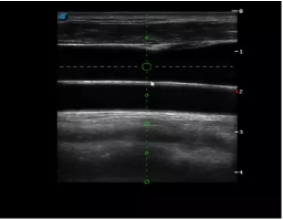

4  置管專(zhuān)用探頭

實(shí)時(shí)觀察穿刺針進(jìn)入血管的全過(guò)程,方便操作及較短的穿刺路徑,智能進(jìn)針尺寸提示,讓置管工作更加輕松,高效。

不同進(jìn)針路徑